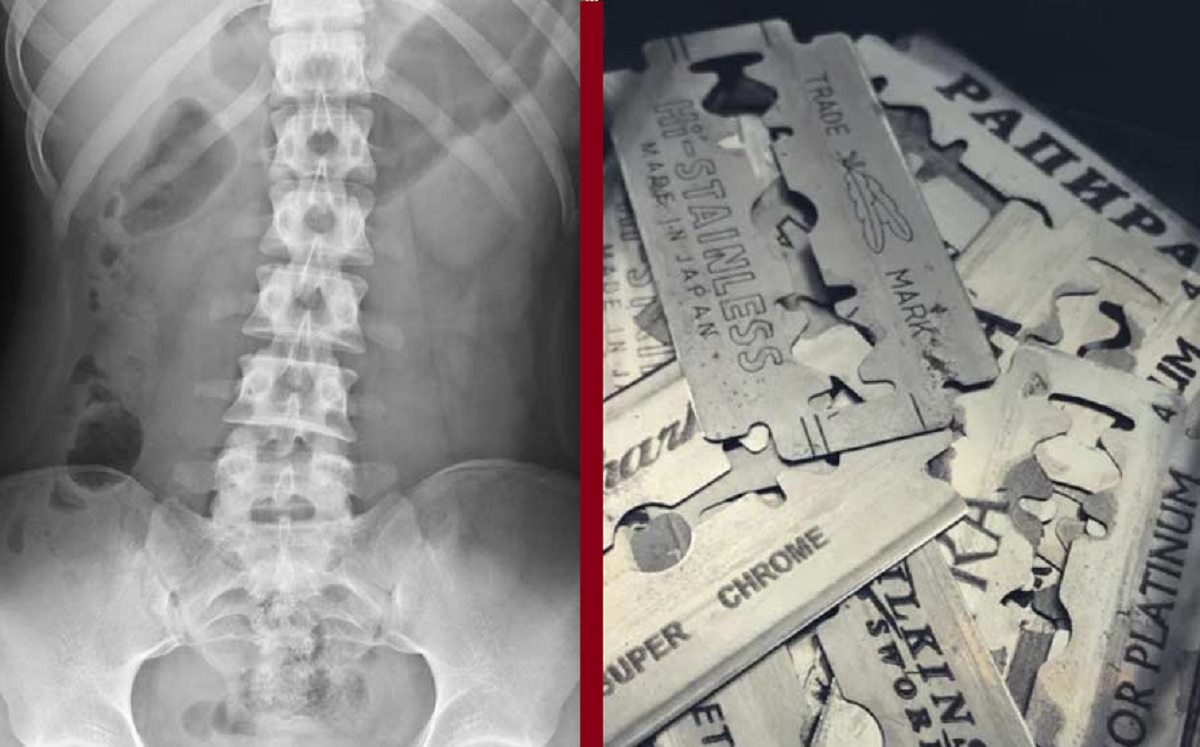

চিকিৎসকরা যুবকের পেট থেকে অস্ত্রোপচার করে বের করলেন ৫৬ টুকরো ব্লেড। কীভাবে একটা মানুষ এতোগুলো ব্লেডের টুকরা খেয়ে ফেললো তা দেখে অবাক হয়েছেন চিকিৎসকরা। ঘটনাটি ঘটেছে ভারতের রাজস্থানে। খবর আনন্দবাজার পত্রিকার।

চিকিৎসকরা জানিয়েছেন, কাউকে না জানিয়েই চুপিসারে দিনের পর দিন ব্লেড খেতেন ওই যুবক। তারপর হঠাৎ গত সোমবার রক্তবমি শুরু হয় তার। তারপর হাসপাতালে নেয়া হলে এক্স-রে, আলট্রাসাউন্ড এবং এন্ডোস্কোপি শেষে দেখা যায়, তার পেটের মধ্যে অসংখ্য ব্লেডের টুকরা রয়েছে। তারপরই সময় নষ্ট না করে অস্ত্রোপচার করার সিদ্ধান্ত নেন ডাক্তাররা।

দীর্ঘ ৩ ঘণ্টার অস্ত্রোপচার শেষে চিকিৎসকরা ওই যুবকের পেট থেকে ব্লেডের ৫৬টি টুকরা বের করেছেন। তারা জানিয়েছেন, ওই যুবক গোটা একটি ব্লেডকে ভেঙে দুটি টুকরা করে গিলে ফেলেন। শরীরের মধ্যে দিয়ে যাওয়ার সময়ে অঙ্গ-প্রত্যঙ্গের ক্ষতি হওয়ায় তার রক্তবমি শুরু হয়। তবে অস্ত্রোপচারের পর যুবকের শারীরিক অবস্থা স্থিতিশীল আছে। কিন্তু এতো খাবার থাকতে হঠাৎ কেন ব্লেড খেতে হলো তাকে? এমন প্রশ্নের কোনো জবাব দেননি ওই যুবক।